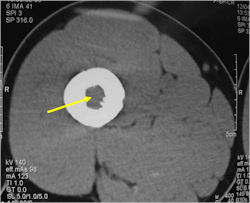

Radiographic Presentation

- Permeative or moth eaten bone destruction

- Ill defined and malignant appearing

- Bony changes are often subtle

- Soft Tissue Mass in 90% of of cases

- Periosteal Reaction in 50% of cases

- Reactive Bone Sclerosis is rare but occurs in 10% of cases

- No cartilage or bone production by tumor